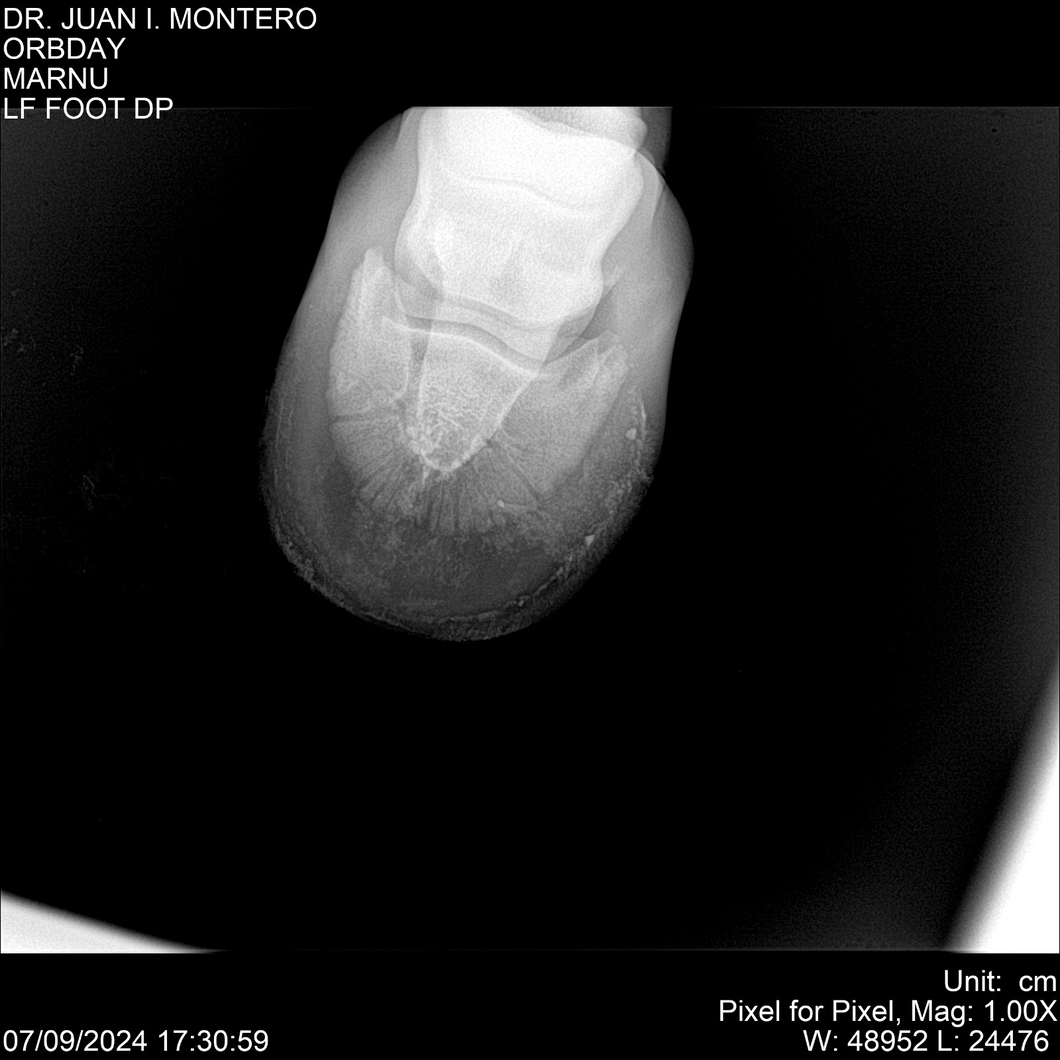

• Empresa: Abelenda N. R., Walter Hugo